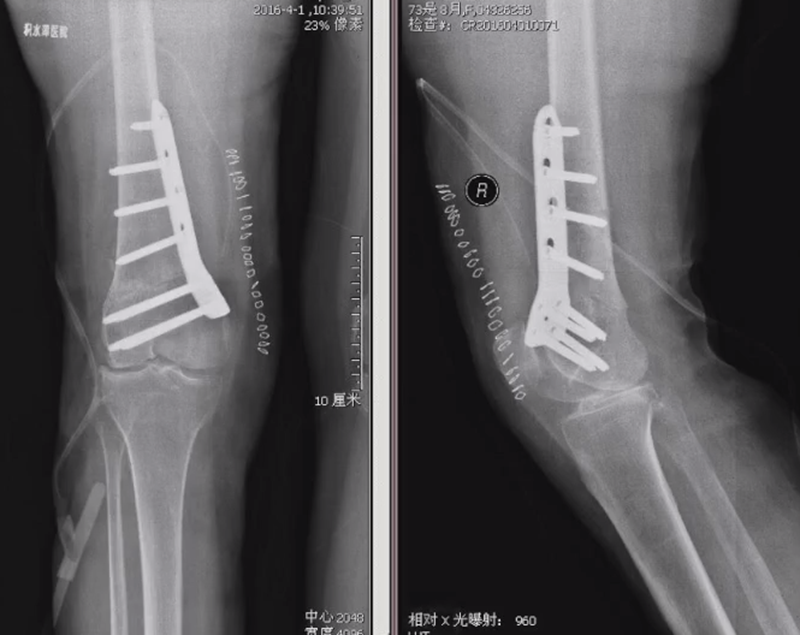

(2)术后力线丢失

对于力线丢失原则是重新矫正力线,重新固定,通常在合页端加上内固定物,主要目的是为了抗旋,有一些截骨端还需要进行植骨。术后早活动晚负重。

病例,X患者,女,双侧外翻膝,行双侧DFO。

术后6周摔伤,一侧出现膝内翻。

影像学检查显示左侧出现合页断裂。

进行翻修,术前力线显示内翻。

术中发现螺钉松动,截骨端出现坎插迹象。

近端螺钉松开,调整力线,重新固定后,在外侧加小钢板抗旋

术后10周复查,力线较好。